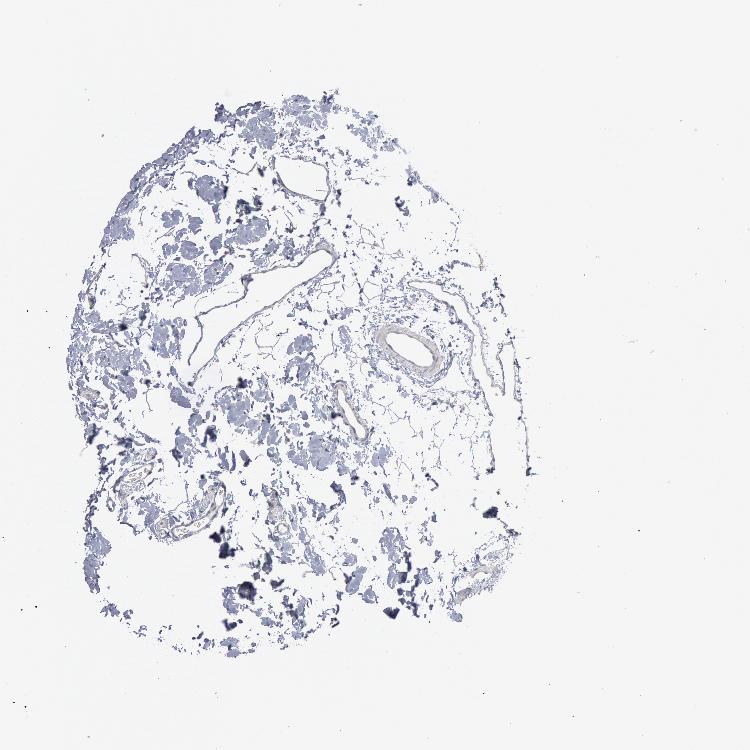

Information about each individual sample is listed below, including gender, age, a tissue section image and estimated fractions of cell types. nTPM (normalized transcripts per million) values give a quantification of the gene abundance which is comparable between different genes and samples.

Male, age 54

Colon sample 67

nTPM: 0.9

Cell types%

Glandular cells:

65

Smooth muscle cells:

10

Other cell types:

25